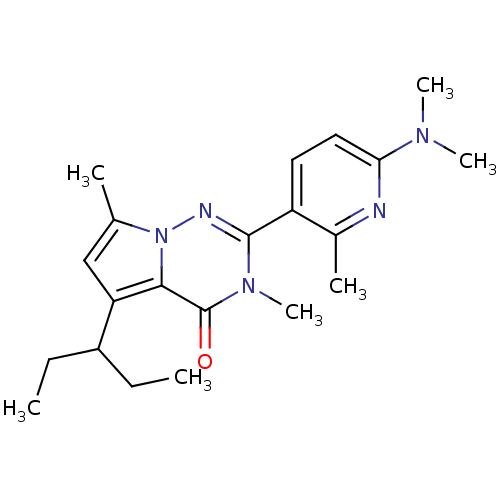

TargetCorticotropin-releasing factor receptor 1(Homo sapiens (Human))

Dupont Pharmaceuticals

Curated by ChEMBL

Dupont Pharmaceuticals

Curated by ChEMBL

Affinity DataEC50: 0.700nMAssay Description:Antagonist activity at human CRF1 receptor expressed in CHO-K1 cells assessed as inhibition of CRF-induced cAMP accumulation after 15 mins by cAMP en...More data for this Ligand-Target Pair